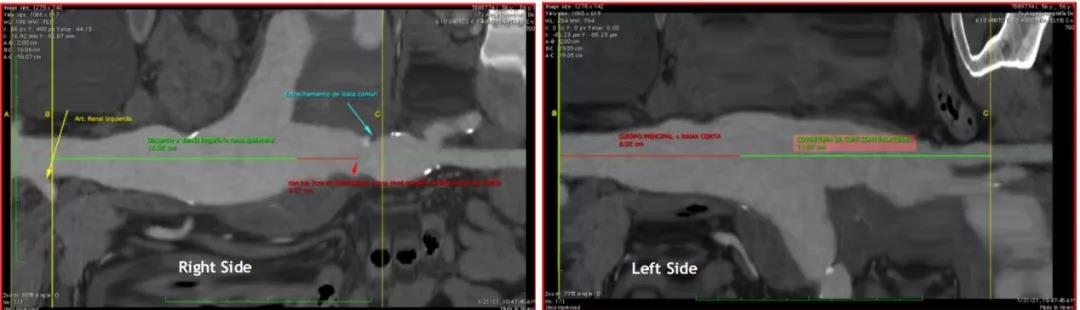

患者为一名56岁男性,CT检查发现为腹主动脉合并双侧髂总动脉瘤。在详细了解并分析患者情况后,郭伟教授建议行腹主动脉腔内支架植入术,同时栓塞左侧髂内动脉,右侧采用彩神在线网信彩票-彩神通免费版下载-彩神8争霸vlll-彩神购彩购彩大厅-彩神软件陆立根免费版-彩神ll争霸3-彩神ll彩神8-彩神ll争霸彩票-拼搏在线彩神网网页版G-iliac™髂动脉分叉支架系统对髂内动脉进行重建。郭伟教授远程连线手术团队,进行了详尽的术前指导,在充分讲解髂动脉分叉支架系统的特点、释放机制及适应症后,郭教授利用主动脉三维重建对手术进行规划,并通过3D打印技术模拟支架植入,提供了支架选型建议等,并对手术难点进行了逐一解析。

(3D 主动脉重建)

(术前CT测量)